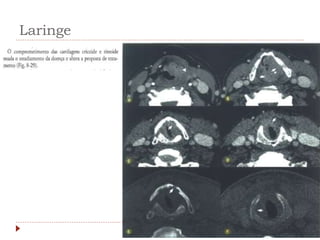

Laringe

 Achados clínicos

 Rouquidão

 Tosse crõnica, dispneia, disfagia.

 CEC: 95-98%

 60% na glote

 30-40% supraglote

 <5% subglote

 Tabagismo e etilismo

Laringe  Achados clínicos Rouquidão  Tosse crõnica, dispneia, disfagia.  CEC: 95-98%  60% na glote  30-40% supraglote  <5% subglote  Tabagismo e etilismo